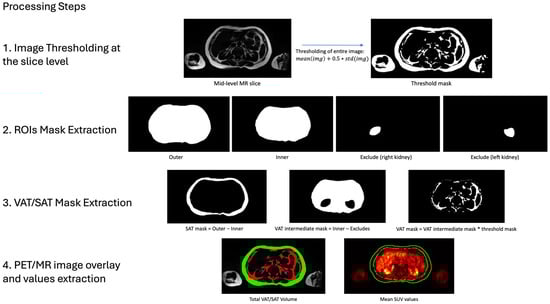

2.4. Volumetric and Metabolic Quantification of Adipose Tissue